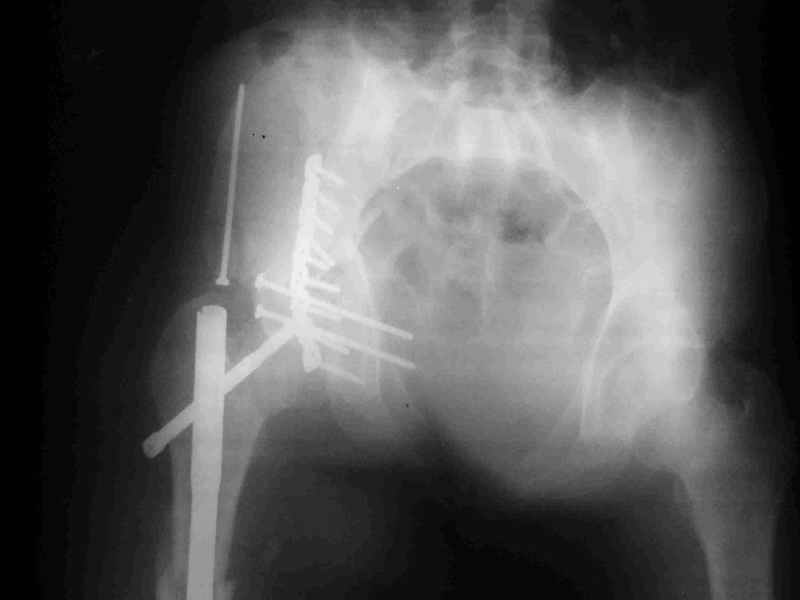

Диагноз- перелом с вовлечением таза, разрыв правого сакро-илиак сочленения vertical shear injury, перелом крыла подвздошной кости?, перелом ацетабулум Т type или Both column?, перелом шейки бедра, перелом проксимального отдела бедра.

перелом крыла правой подвздошной кости, перелом обеих колонн вертлужной впадины, двусторонний перелом лонных костей (С2.2) повреждение передних связок правого крестцово-подвздошного сочленения,

ипсилатеральный перелом шейки и диафиза бедра.

К сожалению, набора для ретроградного или антеградного реконструктивного штифтования в операционной нет, поэтому доставка заняла н-ное время. Вопрос, который возник у меня- по поводу оптимальной тактики хирургии: вся фиксация в один этап из расширенного доступа или последовательно сначала бедро и позже реконструкция впадины, комбинированный доступ к впадине отдельно к передней и задней колоннам или из расширенного илеофеморального одного доступа. Все-таки решил остановиться на одноэтапном подходе и спустя 5 дней (как раз и наборы привезли) из расширенного илеофеморального доступа сначала фиксировал реконструктивным штифтом Smith&Nephews бедро и

шейку (благо перелом шейки 2 типа -относительно стабильный) затем фрагмент крыла подвздошной кости Lag screw, далее пластина на заднюю колонну и винты в переднюю колонну.(с размерами и направлением винтов ошибка вышла:-((, но интраоперационно у меня была полная уверенность , что винты *ушли* в лонную кость).